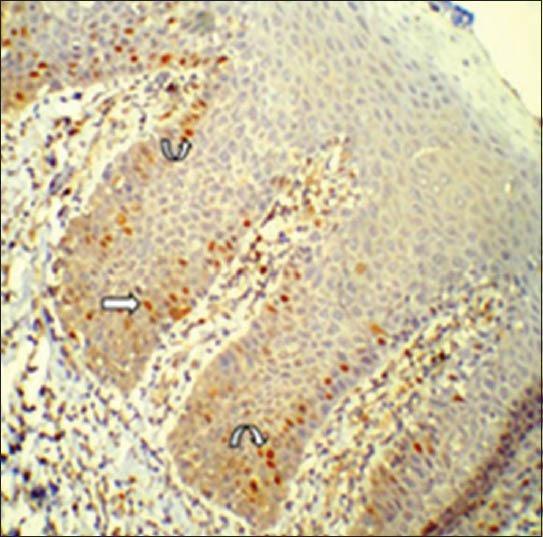

Expression of cyclin D1 in group 3 was significantly higher than in group 1 and 2 (P < 0.001, P = 0.028), expression in group 2 was significantly higher than in group 1 (P = 0.003) and were statistically significant. Generally expression of cyclin D1 was confined to lower one-third of epithelium and was highest in mild dysplasias. Among 13 atypical morphologic features, cyclin D1 expression consistently correlated with basilar hyperplasia.

第3组中细胞周期蛋白D1的表达显著高于第1组和第2组(P < 0.001,P = 0.028),第2组中的表达显著高于第1组(P = 0.003),差异具有统计学意义。一般来说,细胞周期蛋白D1的表达局限于上皮的下三分之一,在轻度发育异常中最高。在13种非典型形态学特征中,细胞周期蛋白D1的表达始终与基底增生相关。